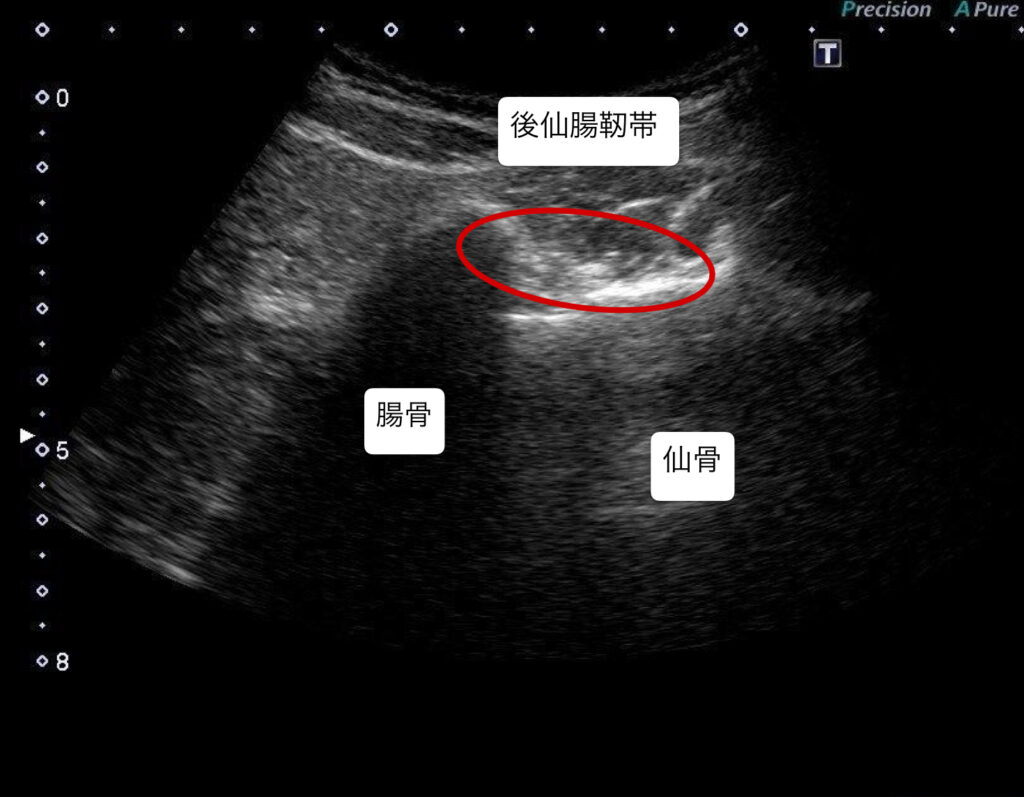

・超音波エコーで観察したところ、腰椎5番目・仙骨1番の椎間関節と仙腸関節の靭帯周囲にファシアの重責がみられた。

・坐骨神経痛の原因が腰椎5番目の神経根周囲の可能性があったため、エコーガイド下L5/S1神経根と後仙腸靭帯に対しエコー下鍼施術、鍼通電を行った。